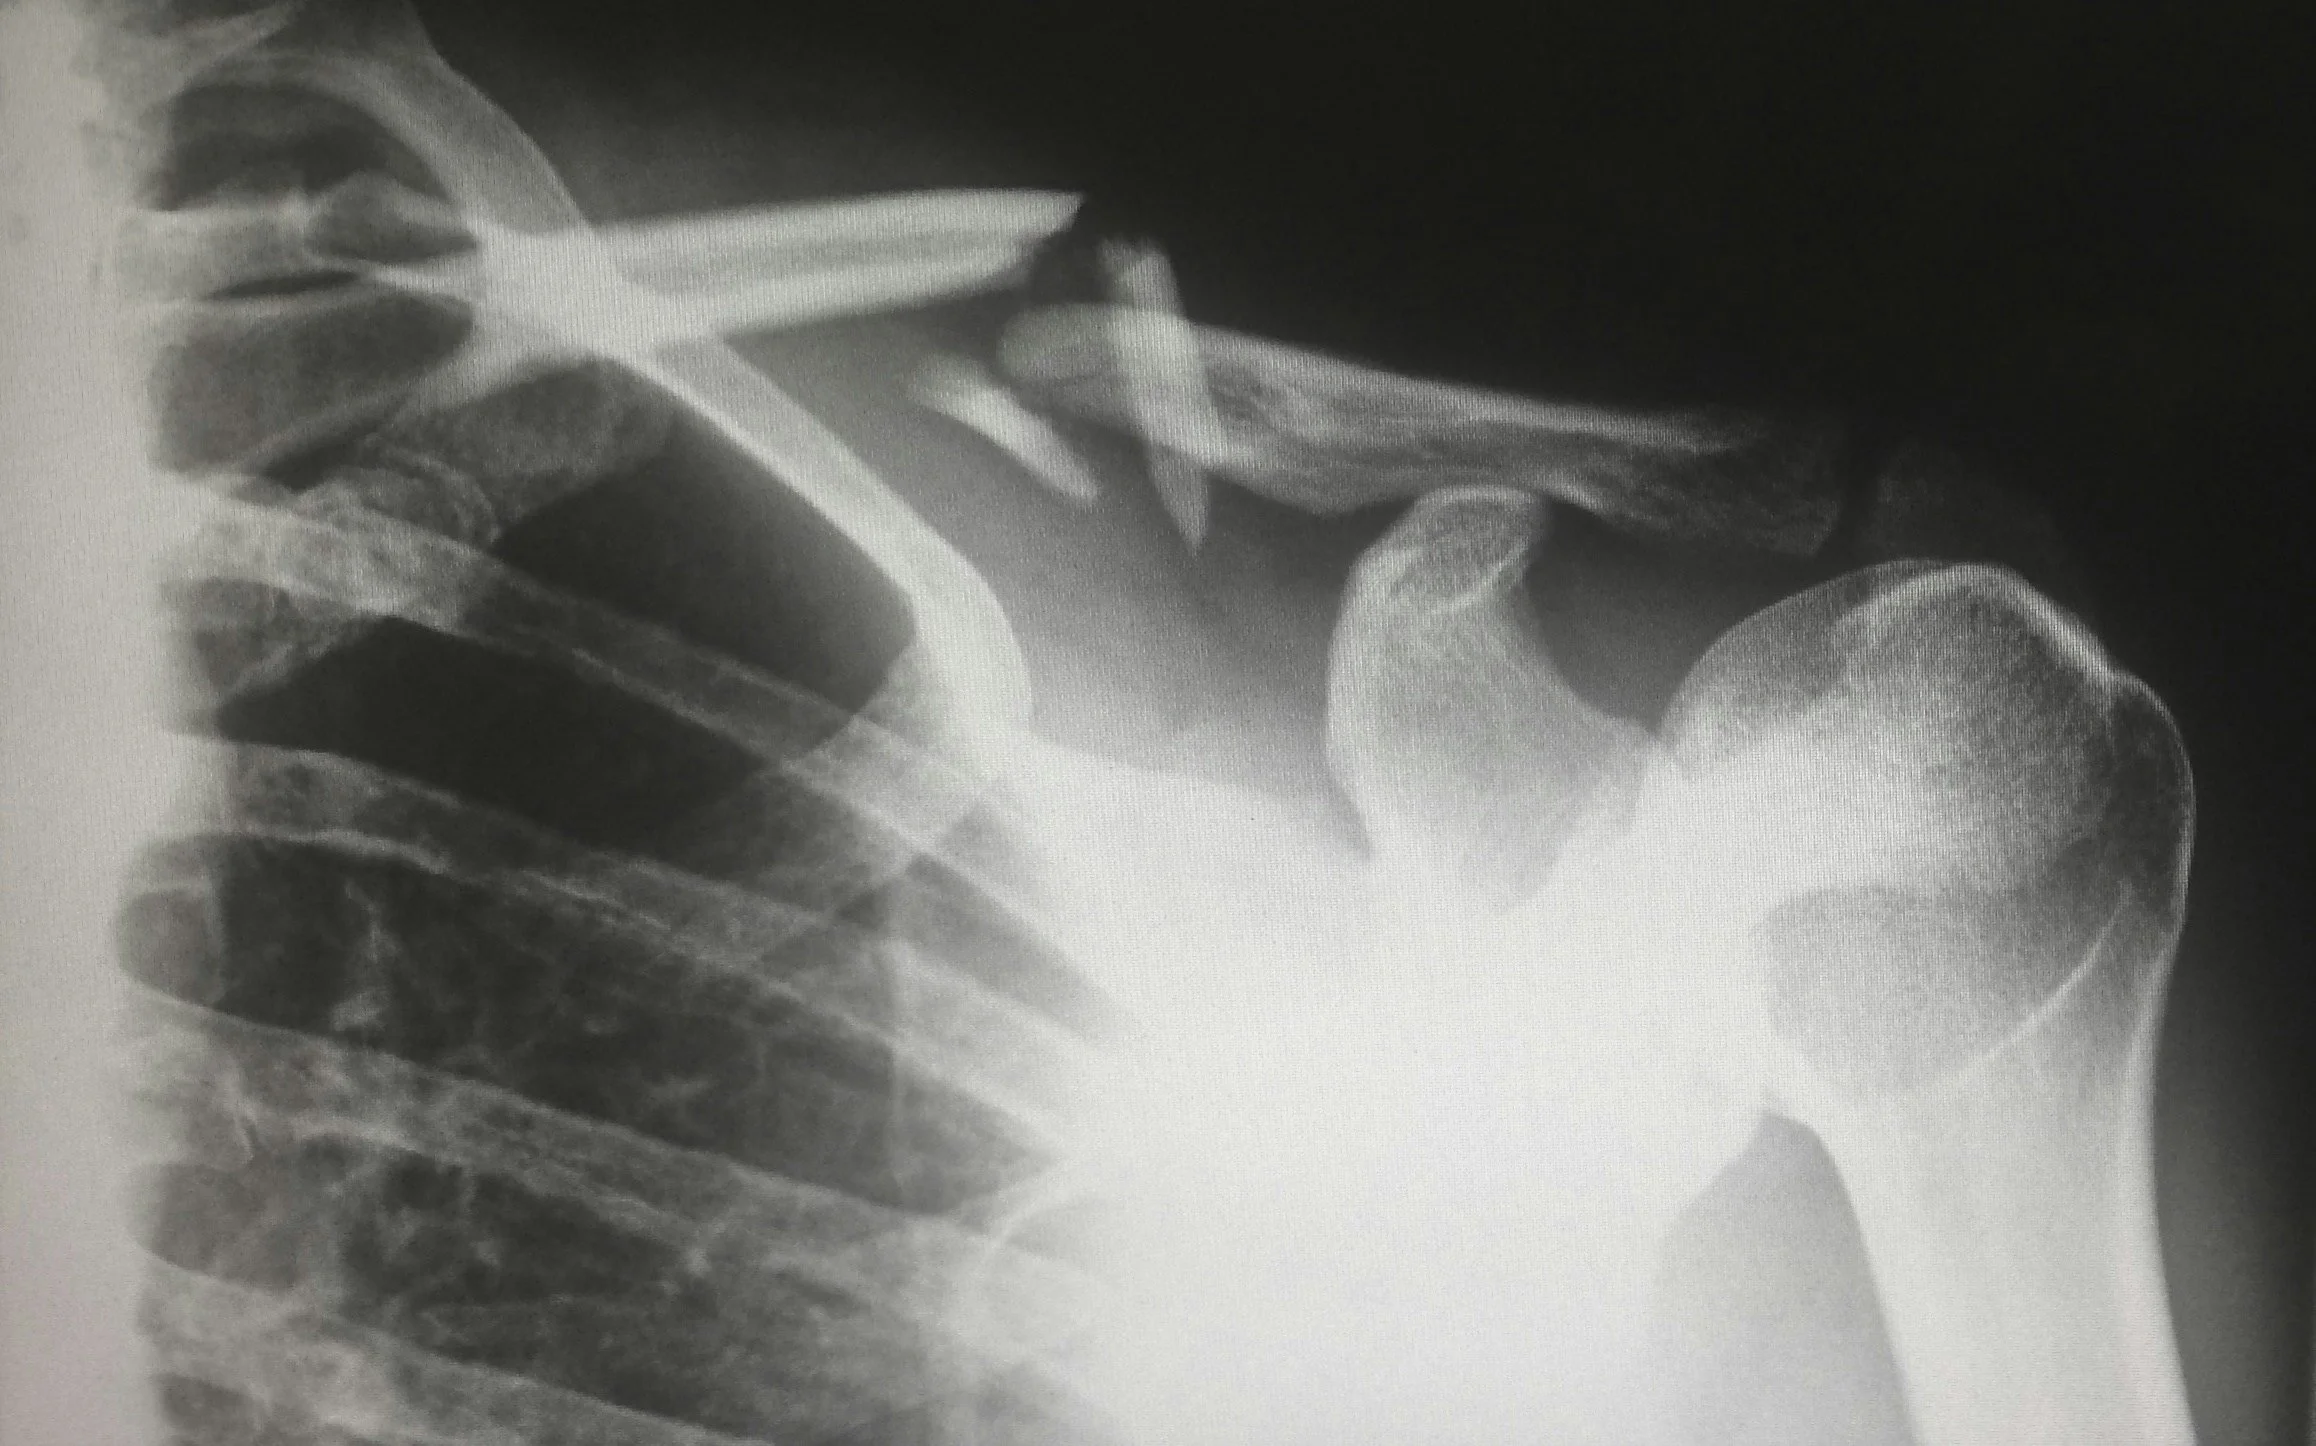

Injuries can significantly disrupt the body’s normal healing processes. Damage to skin, muscle, and underlying tissues often leads to swelling, inflammation, and reduced oxygen supply at the injury site — all of which can slow recovery and increase the risk of complications.

HBOT is widely used in both hospital and outpatient settings to assist recovery from acute and complex injuries, particularly where wounds are deep, traumatic, or slow to heal.